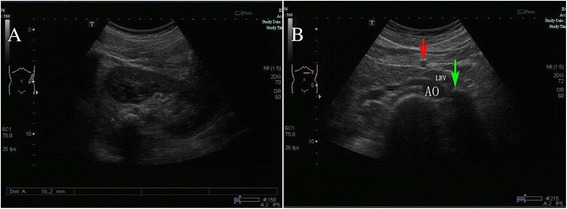

Fig.1.

The images from the ultrasonography. a An abdominal ultrasonography demonstrated 16-mm hyperechoic, echogenic focus in the left renal pelvis. b A color Doppler ultrasonography indicated the hyperechoic focus (green arrow) in the left renal vein (LRV). Aorta (AO); left renal vein (LRV); superior mesenteric artery (red arrow)

Due to left lower back pain and the persistent left hyperechoic focus in the renal area, the patient was referred to our hospital for further evaluation and treatment. Urine analysis and ultrasound examination showed the same results as in the regional hospital (Fig. 1a). An abdominal plain film showed a left-sided renal calcification (Fig. 2a), but there was no evidence of a palpable tender mass or an audible abdominal bruit. Laboratory data, except for urinalysis results, were within normal limits. Because of the failure of extracorporeal shock wave lithotripsy, percutaneous lithotomy was recommended.

Because the shape of the calculus was unusual and there was no evidence of hydronephrosis, the diagnosis of calculus was questioned. Further evaluation to determine the true nature of the hyperechoic lesion included computed tomography (CT) without contrast, which showed the calculus in the left ureter (Fig. 3a). In addition, intravenous pyelography showed that the pelvic areas around both kidneys were normal, although a patchy shadow was observed above the left renal pelvis (Fig. 2b). Color Doppler ultrasonography showed the hyperechoic focus in the left renal vein (Fig. 1b). CT angiography indicated a hyperdense mass in the left renal vein, suggesting a calcified thrombus, as well as occlusion of the left renal vein, varicosity in the left ovarian vein, and peripheral veins around the left renal hilum (Fig. 3b–d).

In diagnosing RVT, ultrasound imaging and Doppler ultrasonography are not recommended because their results are inconsistent and operator-dependent. Ultrasound scans may show an enlarged kidney, and a hyper-echogenic kidney is observed in approximately 90 % of patients during the early phase of acute RVT [9]. Color Doppler ultrasound is ineffective in detecting segmental venous thrombosis, but is superior to conventional ultrasound and abdominal plain film in detecting flow in the renal artery and vein. Although color Doppler ultrasound is highly sensitive when performed by an experienced operator, but remains highly operator-dependent [8]. Rarely, the calcified vessel walls of the renal venous branches coursing through the sinus may be mistaken for a renal calculus on ultrasonography. In the patient described here, there was no evidence of turbulent flow within the calcified RVT. Thus, RVT was not considered in the initial evaluation, although subsequent color Doppler yielded results suggestive of RVT.